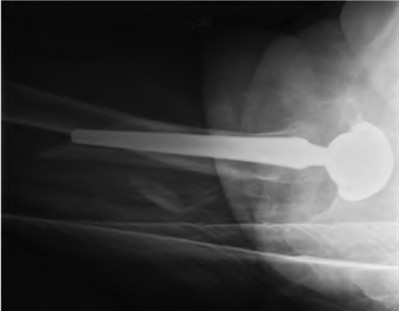

A 72-year-old male presents 2 years status post fixation of an impending pathologic right femur fracture due to metastatic renal cell carcinoma. He is minimally ambulatory due to pain. Despite radiation therapy, there has been progression of the lesion with extensive cortical bone loss, which is shown in Figure A. A proximal femoral replacement arthroplasty is performed without complications, and is demonstrated in Figure B. Which of the following is true regarding this patients post-operative course?

Figure A shows a lytic lesion of the proximal femur with an intramedullary implant. Figure B shows a proximal femoral replacement.